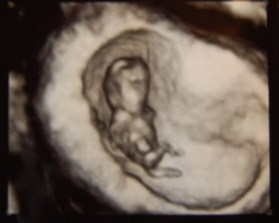

Ville lige dele et af billederne af den fine, lille bønne, der ligger og spjætter inden i min mave

Blev i dag skudt til at være i uge 10 + 0 eller 10 + 1 = fin vækst.